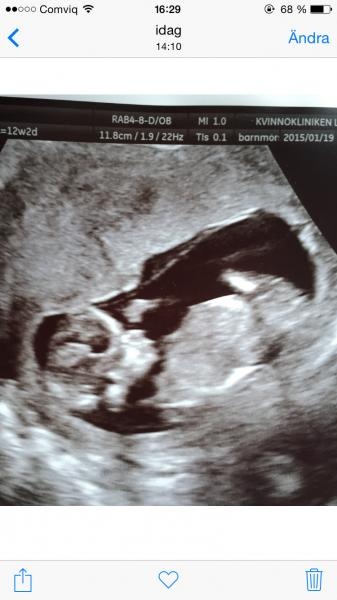

Det gick super! Vilken känsla att se sin bebbe första gången! H*n sprallade som attan och fick 1:20.000 så allt var tipp topp

Det gick super! Vilken känsla att se sin bebbe första gången! H*n sprallade som attan och fick 1:20.000 så allt var tipp topp smile2.gifphp4kVsUe49674.jpg